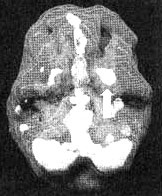

Мозг Марка — посттравматический стресс и головные боли

Иллюстрация к книге — Измените свой мозг - изменится и жизнь! [i_040.jpg]

Трехмерное изображение — активный мозг, вид снизу. Обратите внимание на повышенную активность базальных ганглиев слева (помечено стрелкой).

Результаты вышли за рамки нормы. Мы обнаружили значительно повышенную активность базальных ганглиев в левой части мозга. Такой гиперактивности в этой области мне прежде видеть не доводилось. Левосторонние нарушения функций базальных ганглиев часто встречаются у людей, которые постоянно находятся в раздраженном или гневном состоянии. В этих случаях помогают препараты, стабилизирующие настроение, — такие, как литий, Tegretol или Depakote, снижающие раздражительность и помогающие успокоить «разогретые» участки в головном мозге. Марку я назначил Depakote. Почти сразу прекратились головные боли, а сам он стал спокойнее. Он прекратил «кидаться» на окружающих и стал способен заняться своим психологическим выздоровлением после развода и травм, полученных во Вьетнаме.

Во время работы с Марком у меня сложилось впечатление, что пребывание во Вьетнаме перепрограммировало его базальные ганглии на постоянную работу в режиме «начеку». На протяжении всех 13 месяцев, которые он провел на войне, каждый день он должен был оставаться «начеку», чтобы его не убили. Все последующие годы у него не было возможности перепрограммировать свой мозг для работы в нормальном режиме. Психотерапия и лекарства помогли ему ощутить, впервые за последние 25 лет, что он на самом деле вышел из зоны боевых действий.